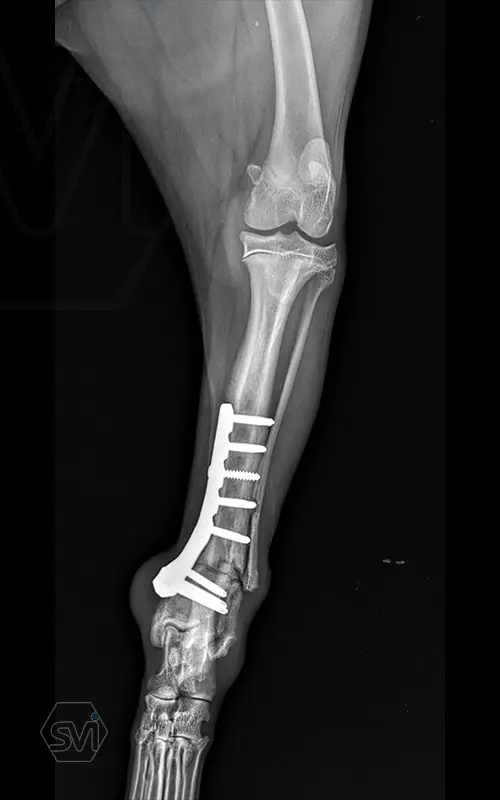

Multifunctional symmetrical long polyaxial locking plate - designed for the treatment of fractures close to joints

A special member of the polyaxial locking plate family is the multifunctional long plate, which is an extended version of the well-known symmetrical TPLO plate, with a 5-3 hole distribution. The plate also received a DCP hole to be able to create compression, and there is a mini-hole on the head end to facilitate the placement of the temporarily used K-nail. The burrs on the side facing the bone surface are intended to reduce the contact surface between the plate and the bone (limited contact).

The plate is a member of the large polyaxial locking family, suitable for 2.7-3.5-4.0 mm screws. We recommend it for fixaton of fractures close to joints, wedge osteotomies with axis correction (closing and opening), or for CWTO operations.